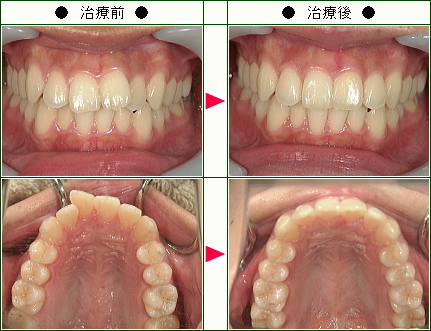

☆歯のデコボコ矯正症例(Y様 38歳 女性)